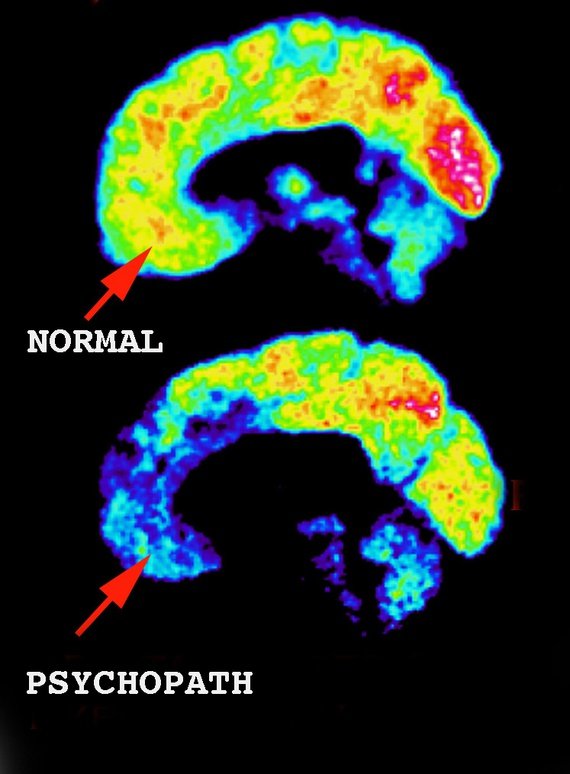

사이코패스와 일반인의 뇌 비교

뇌의 앞부분(전전두피질, 의사결정, 사회적 행동, 성격 표현)과 가운데 작은 영역(감정을 담당하는 편도체)은 사이코패스의 뇌에서 불이 들어오지 않는 것이 보인다. 이러한 영역에서 활동이 거의 또는 전혀 없음을 의미한다.

실제로 이러한 차이점에 대해 진행한 여러 연구들이 있다. 연구 결과는 감정과 사회적 행동을 조절한다고 믿어지는 뇌의 두 구조가 제대로 소통하지 못하는 것을 보여준다.

사이코패스의 뇌는 사이코패스가 사회의 작은 부분을 대표하면서도 심각한 범죄 행위를 저지른다는 사실 때문에 수십 년 동안 연구의 관심 대상이었다. 자기 공명영상(MRI) 스캔 또는 기능적 MRI(fMRI) 스캔을 받는 사이코패스가 점점 더 많아짐에 따라 몇 가지 상관관계가 발견되었다. 확실히 사이코패스의 뇌는 일반 뇌와 다르다.

사이코패스의 뇌 스캔 결과에서 큰 차이를 보이는 세 가지 주요 부분이 있다. 편도체, 전두엽 피질 및 확장된 변연계 구조의 영역이다. 이 영역에 미치는 영향은 정신병적 증상을 유발하는 것일 수 있으며 정신병적 성격이라고 진단 내릴 수 있는 기준이 된다.